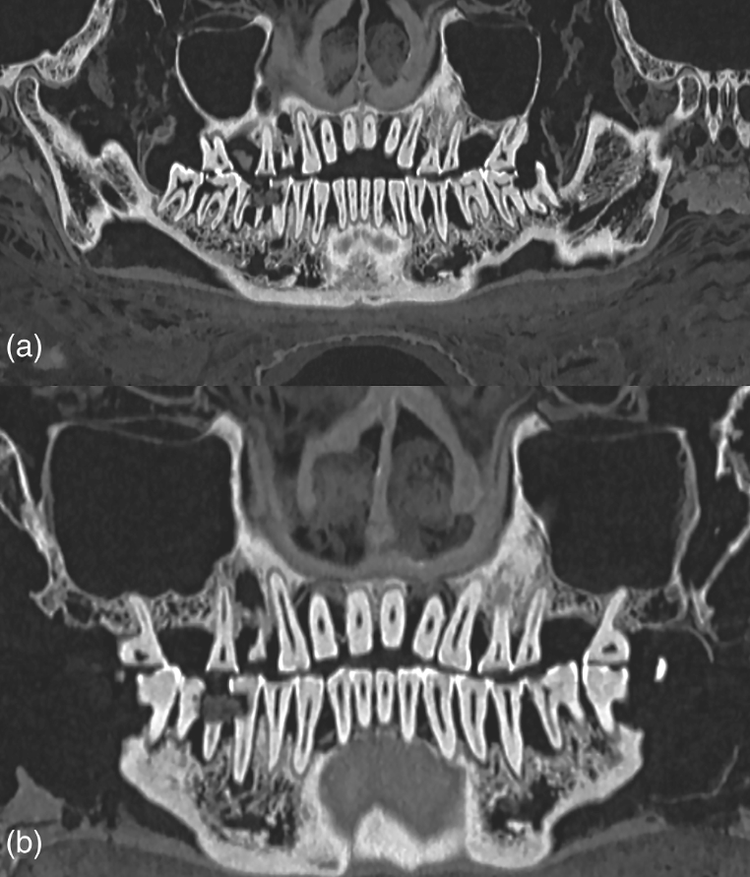

Để có được kết luận này, các chuyên gia đã sử dụng kỹ thuật chụp cắt lớp vi tính (CT) để mô tả đầy đủ về răng xác ướp Ai Cập. Ảnh: @Bảo tàng Khảo cổ học Quốc gia Athens. Các nhà nghiên cứu đã tìm thấy một khoang xốp trong răng của xác ướp này chứa đầy vật liệu trám bảo vệ. Ảnh: @Bảo tàng Khảo cổ học Quốc gia Athens. Tất nhiên, việc trám răng như vậy được thực hiện như một hình thức trị liệu chứ không phải là một phần của quá trình ướp xác. Ảnh: @Bảo tàng Khảo cổ học Quốc gia Athens.

Ngoài ra, các nhà khảo cổ học cũng tìm thấy bằng chứng về tình trạng nhiễm trùng nướu nghiêm trọng trên xác ướp này. Nghiên cứu không tập trung vào nguyên nhân cái chết của xác ướp, nhưng đặc điểm của hộp sọ cho thấy nó thuộc về một người đàn ông trưởng thành, qua đời ở độ tuổi đôi mươi. Ảnh: @Bảo tàng Khảo cổ học Quốc gia Athens. Mời Quý Độc Giả cùng xem video: “Phát hiện hơn 100 mộ táng thời kỳ Hùng Vương có niên đại khoảng 3.500 năm tại Di chỉ Vườn Chuối”. Nguồn video: @VTV24.